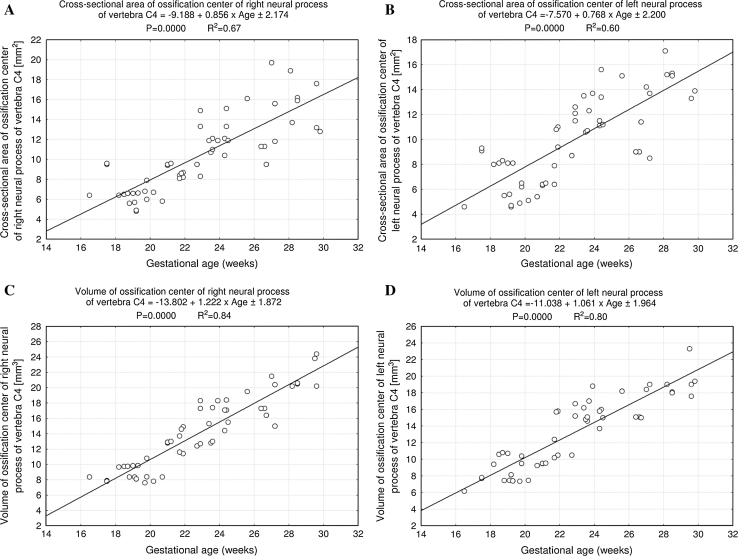

Fig. 8.

Regression lines for cross-sectional area on the right (a) and left (b) and for volume on the right (c) and left (d) of the ossification center of the neural processes

The size of ossification centers of the neural processes has been listed in Table 4. Although the right–left differences for the entire group were not statistically significant, the results have already been presented separately for each neural process, because of their great inter-individual variability. The ossification center of the neural process grew in length from 3.40 to 7.55 ± 0.32 mm on the right (Fig. 7a), and from 3.49 to 7.38 ± 0.30 mm on the left (Fig. 7b), in correspondence with the logarithmic functions: y = −19.601 + 8.018 × ln (Age) ± 0.369 (R 2 = 0.92) and y = −15.804 + 6.912 × ln(Age) ± 0.471 (R 2 = 0.85), respectively. Its width increased from 1.66 to 2.67 ± 0.27 mm on the right (Fig. 7c), and from 1.62 to 2.59 ± 0.32 mm on the left (Fig. 7d), following the logarithmic functions: y = −5.806 + 2.587 × ln(Age) ± 0.146 (R 2 = 0.88) and y = −5.621 + 2.519 × ln(Age) ± 0.146 (R 2 = 0.88), respectively. The cross-sectional area of the ossification center for the neural process revealed an increase from 6.40 to 18.05 ± 7.36 mm2 on the right (Fig. 8a), and from 4.60 to 15.03 ± 5.60 mm2 on the left (Fig. 8b), as the linear functions: y = −9.188 + 0.856 × Age ± 2.174 (R 2 = 0.67) and y = −7.570 + 0.768 × Age ± 2.200 (R 2 = 0.60), respectively. The growth in volume of the right (Fig. 8c) and left (Fig. 8d) ossification centers of the neural processes varied from 8.37 to 21.53 ± 3.15 mm3, and from 6.17 to 19.83 ± 2.44 mm3, respectively, following the linear functions: y = −13.802 + 1.222 × Age ± 1.872 (R 2 = 0.84), and y = −11.038 + 1.061 × Age + 1.964 (R 2 = 0.80).